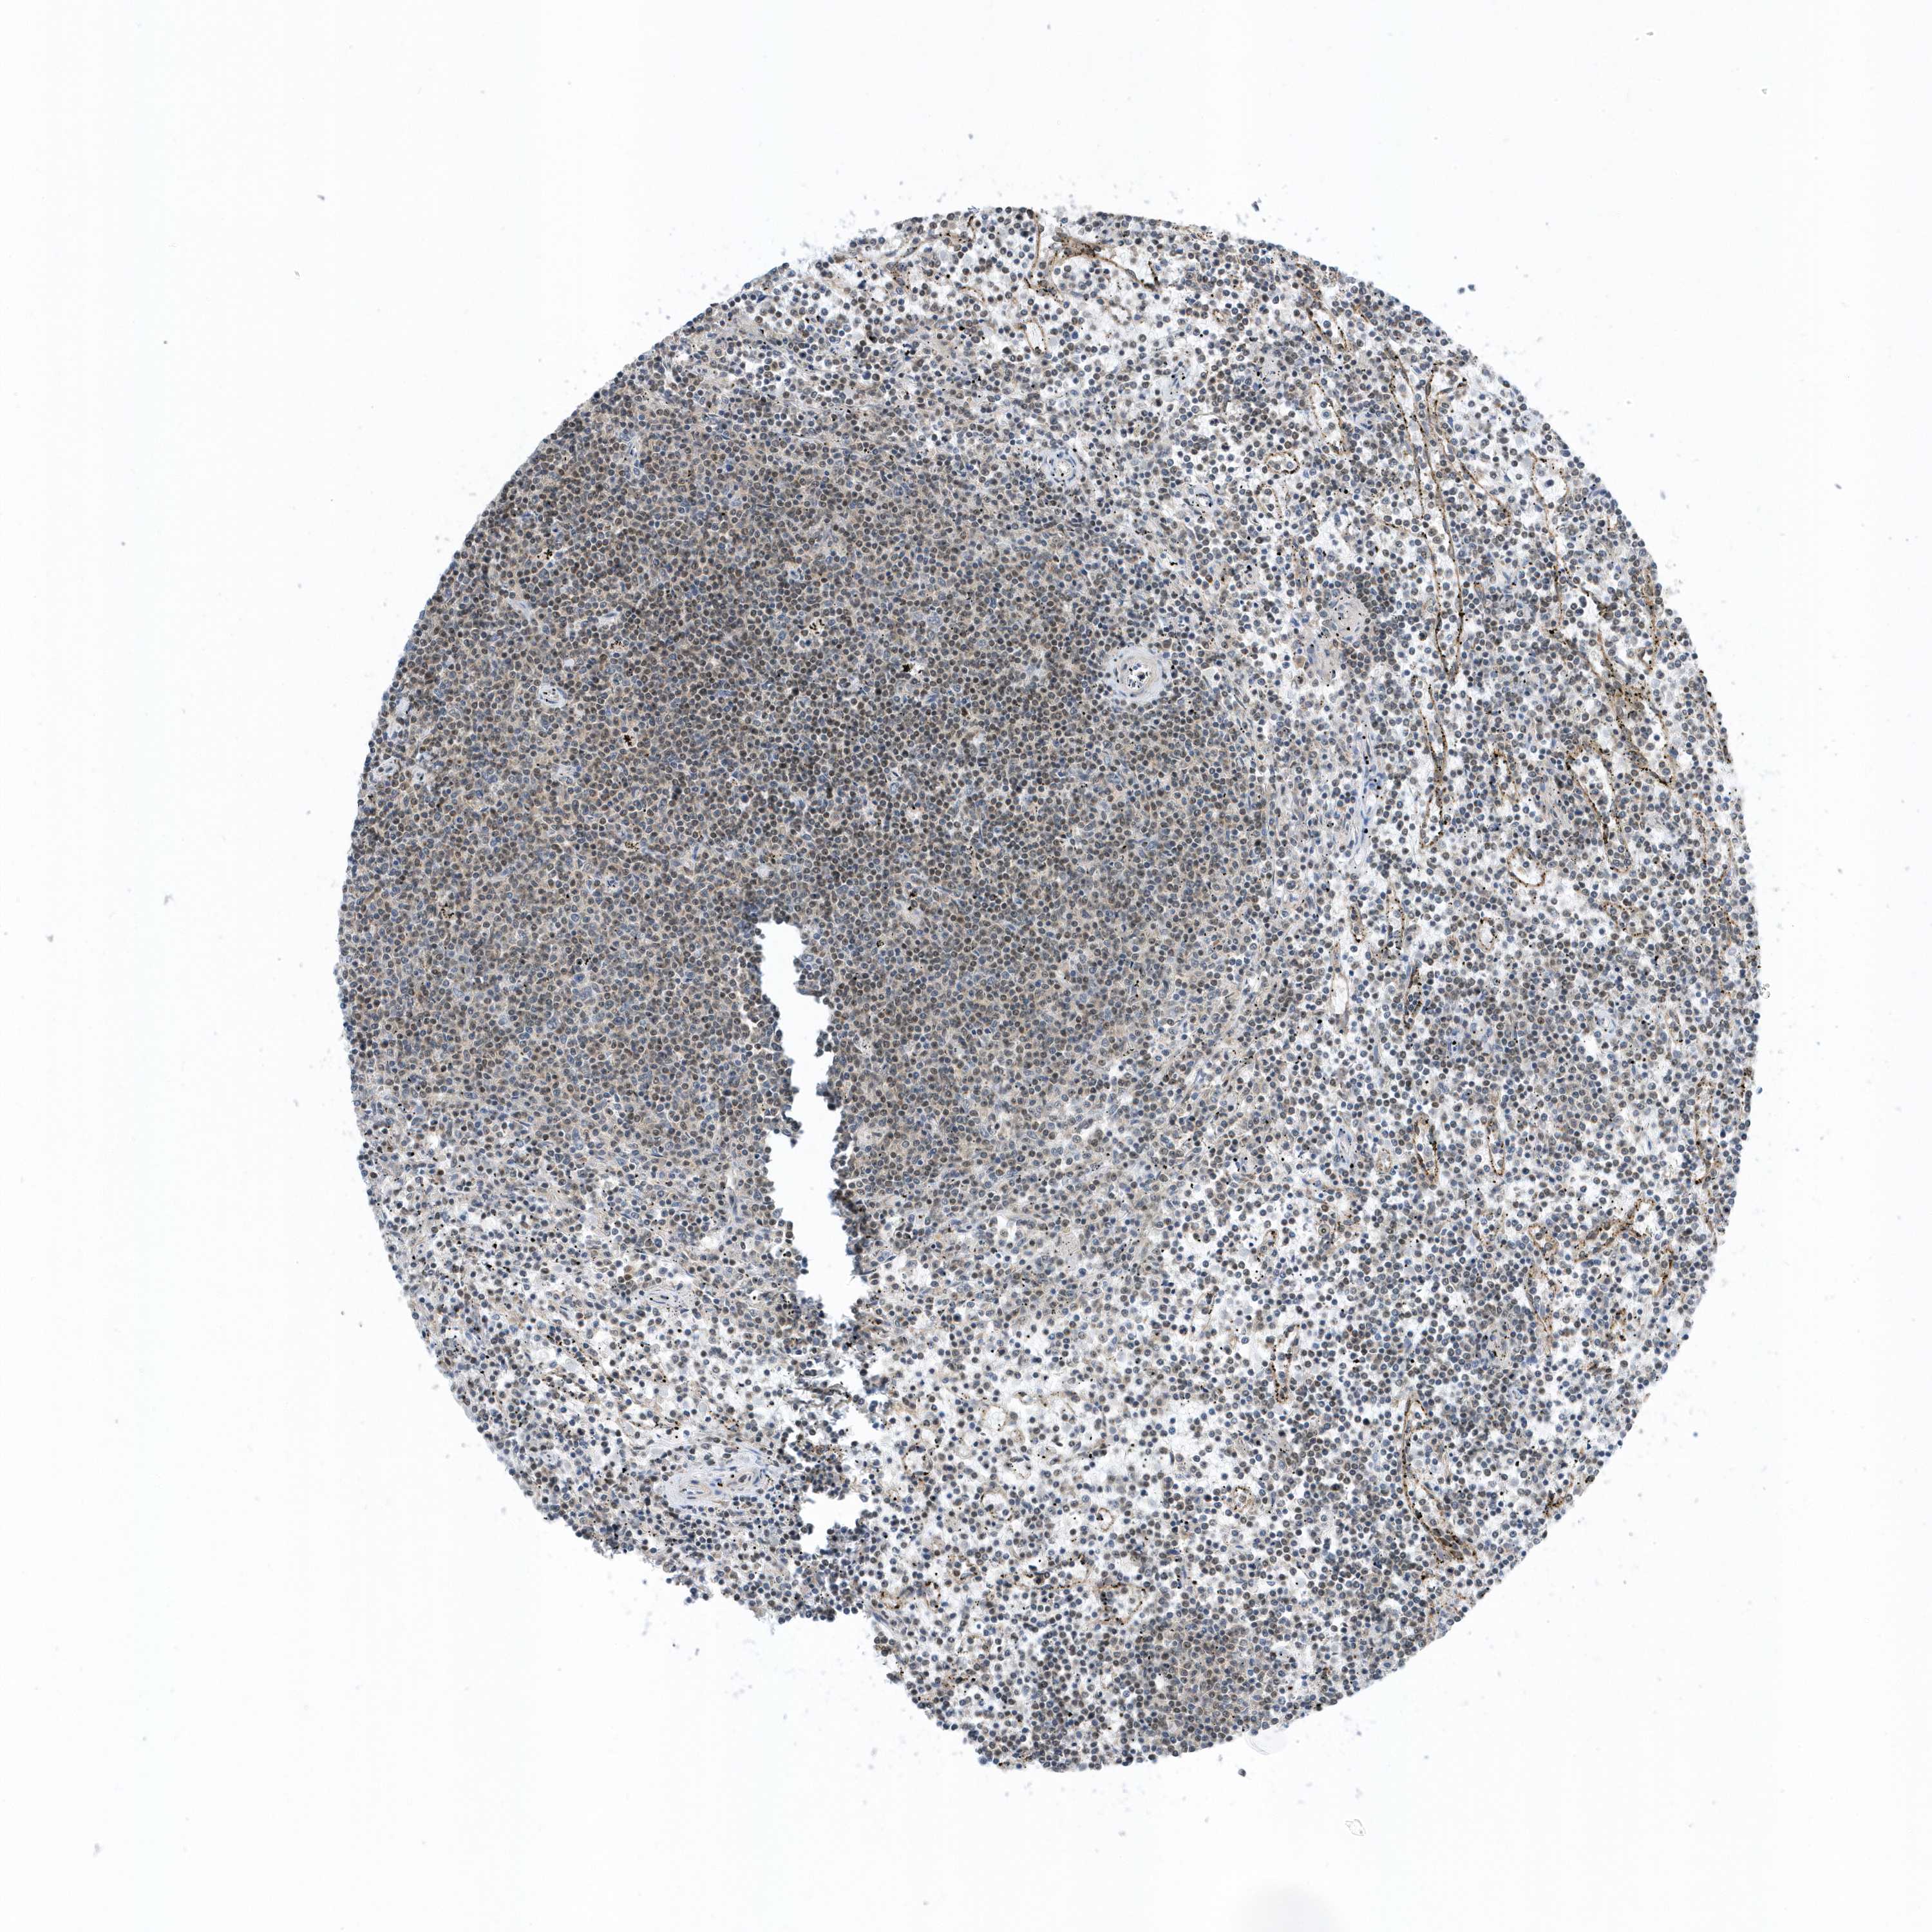

LYMPHOMA - Protein expressioni

A mouse-over function shows sample information and annotation data. Click on an image to view it in a full screen mode. Samples can be filtered based on level of antibody staining by selecting one or several of the following categories: high, medium, low and not detected. The assay and annotation is described here.

Antibody stainingi

Antibody staining in the annotated cell types in the current human tissue is reported as not detected, low, medium, or high, based on conventional immunohistochemistry profiling in selected tissues. This score is based on the combination of the staining intensity and fraction of stained cells.

Each image is clickable and will lead to virtual microscopy that enables deeper exploration of all samples and also displays staining intensity scores, fraction scores and subcellular localization as well as patient and tissue information for each sample.

Antibody HPA035691

Staining

High

Medium

Low

Not detected

Intensity

Strong

Moderate

Weak

Negative

Quantity

>75%

75%-25%

<25%

None

Location

Nuclear

Cytoplasmic/membranous

Cytoplasmic/membranous,nuclear

Hodgkin's disease, NOS

Malignant lymphoma, non-Hodgkin's type, High grade

Malignant lymphoma, non-Hodgkin's type, Low grade